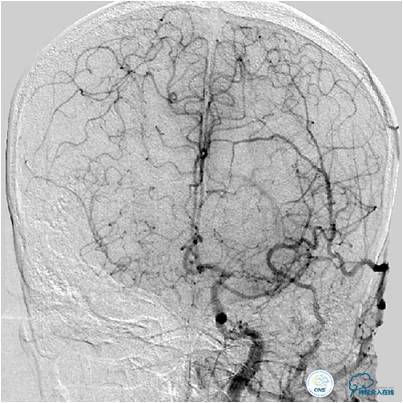

图3B:左侧颈内动脉造影动脉晚期提示双侧大脑半球染色尚可,右侧大脑中动脉供血区由右侧大脑前动脉的软脑膜动脉代偿。